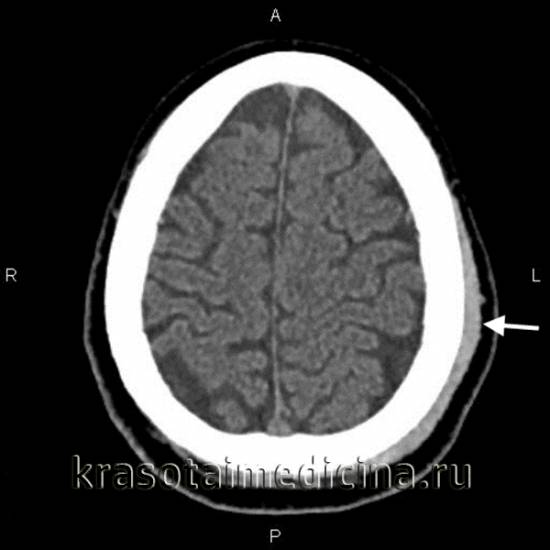

КТ головного мозга: гематома периферических мягких тканей левой теменной области.

image